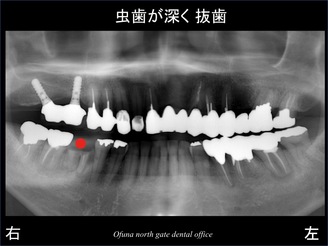

最近になり、下顎右側の奥歯が取れて来院されました。

取れた歯は、虫歯が深く、抜歯となりました。

この歯を抜歯後にインプラントを埋入したのが以下のレントゲンです。